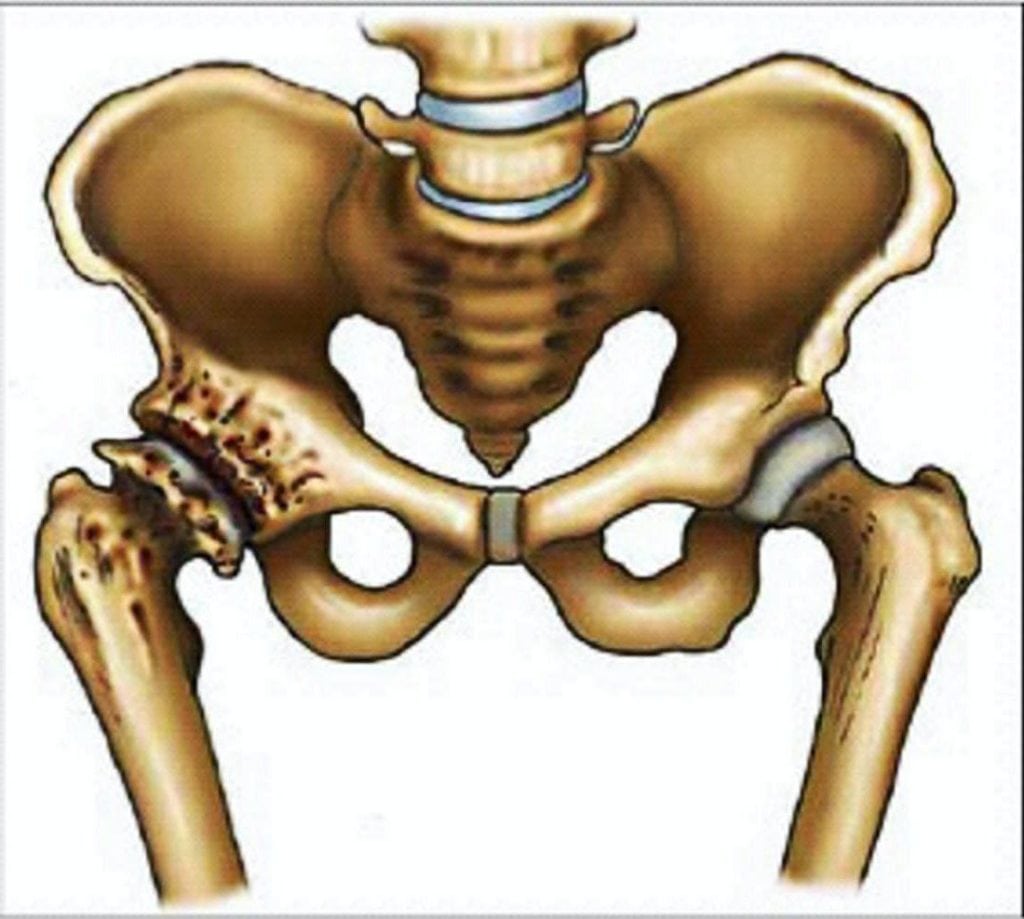

Частой причиной болей в бедре становится коксартроз, или остеоартроз тазобедренного сустава. Дегенеративно-дистрофическая патология при отсутствии врачебного вмешательства медленно, но упорно прогрессирует. На начальной стадии коксартроза дискомфортные ощущения выражены слабо, возникают при повышении двигательной активности. По мере разрушения гиалинового хряща и истирания костных поверхностей боли усиливаются, возникают даже в состоянии покоя. Они сопровождаются хрустом и щелчками в суставе, его утренней отечностью и скованностью движений. Спустя некоторое время интенсивность болей вновь снижается. Это ни в коем случае не свидетельствует о выздоровлении — суставная щель срастается, и врачи диагностируют анкилоз — полное обездвиживание тазобедренного сочленения.